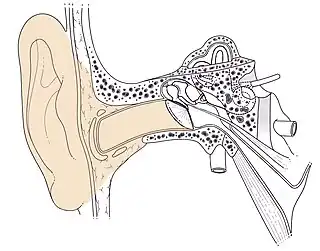

Conduit auditif externe droit Schéma